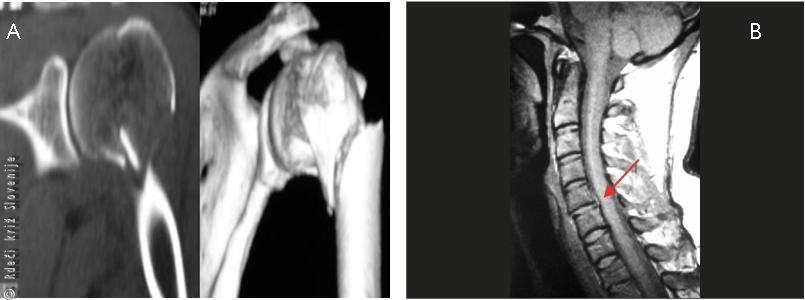

Vsakega poškodovanca, pri katerem sumimo, da bi lahko prišlo do zloma, napotimo na rentgensko slikanje. Vsako kost slikamo v dveh projekcijah: od spredaj navzad (anteroposteriorna projekcija) in od strani (lateralna projekcija). Pomembno je, da na vsaki sliki prikažemo tudi sosednja sklepa. Občasno so potrebne tudi posebne projekcije (poševne, polstranske ipd.). Pri sklepnih zlomih, pri zlomih obraznih kosti, medenice in hrbtenice si pomagamo s slikanjem po plasteh (tomografija), ki nam omogoči prikaz poškodovanega dela v seriji prerezov. Včasih se je uporabljala klasična tomografija, danes pa večinoma opravimo računalniško tomografijo (CT), ki omogoča tudi natančno rekonstrukcijo kosti v dveh ali treh ravninah. Pri poškodbah hrbtenice nam veliko pove tudi slikanje z magnetno resonanco (MR), saj te slike natančno prikažejo hrbtenjačo, prikažejo pa tudi ostala mehka tkiva, ki jih na RTG slikah ne vidimo.

Slika 13

A – CT slika ramena in 3D slikovna diagnostika, ki sta natančno pokazali položaj zloma glave nadlahtnice.

B – MR slika vratne hrbtenice: šele na tej sliki so lahko ugotovili pomik in pritisk medvretenčne ploščice.